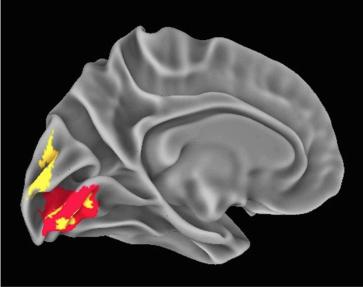

Researchers at the National Institute of Mental Health (NIMH) have produced the first direct evidence that parts of our brains implicated in mental disorders may be shaped by a "residual echo" from our ancient past. The more a person's genome carries genetic vestiges of Neanderthals, the more certain parts of his or her brain and skull resemble those of humans' evolutionary cousins that went extinct 40,000 years ago, says NIMH's Karen Berman, M.D. NIMH is part of the National Institutes of Health.

In particular, the parts of our brains that enable us to use tools and visualize and locate objects owe some of their lineage to Neanderthal-derived gene variants that are part of our genomes and affect the shape of those structures -- to the extent that an individual harbors the ancient variants. But this may involve trade-offs with our social brain. The evidence from MRI scans suggests that such Neanderthal-derived genetic variation may affect the way our brains work today -- and may hold clues to understanding deficits seen in schizophrenia and autism-related disorders, say the researchers.

The new MRI evidence points to a a gene variant shared by modern-day humans and Neanderthals that is likely involved in development of the brain's visual system. Similarly, Neanderthal variants impacting development of a particular suspect brain area may help to inform cognitive disability seen in certain brain disorders, say the researchers.